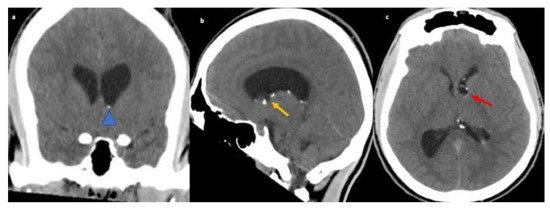

A 26-year-old African-American male with no significant medical history presented to the ED with decreased level of consciousness complaining of severe headache, nausea, vomiting and bowel and bladder incontinence for one day. The patient underwent emergent CT Head and CT angiogram to rule out subarachnoid hemorrhage. CT Head showed ventriculomegaly and diffuse sulcal effacement concerning for edema. A 9 × 6 mm fluid density lesion in the frontal horn of left lateral ventricle adjacent to the foramen of Monro with peripheral calcification was identified (yellow and red arrow), leading to obstructive supratentorial hydrocephalus (blue arrow head and yellow arrow). Additional scattered hyperdensities were also seen along the left lateral ventricular wall (refer Figure 3).

Figure 3.

CT Head non-contrast coronal (a) reveals small punctuate foci of calcification along the left lateral ventricle (blue arrow head). Additional CT head sagittal and axial (b,c) reveals 9 mm × 6 mm fluid density lesion in the frontal horn of left lateral ventricle with peripheral calcification near foramen of Monro (yellow and red arrow) leading to obstructive supratentorial hydrocephalus. Additional small punctuate foci of calcification along the left lateral ventricle.

The patient underwent external ventricular drain (EVD) placement with opening pressure of 22 cm of water and underwent surgery for removal of the lesion at the foramen of Monro. Pathology report from the biopsy of the lesion revealed choroid plexus with predominantly non-caseating granulomatous inflammation and intraventricular calcifications. A gradual improvement in mentation was noted following the procedure. He also showed improvement in headache.

Laboratory workup was unremarkable for infectious or other autoimmune markers. CSF studies were remarkable only for elevation in CSF protein (67 mg/dL). The patient was then started on prednisone after post-biopsy confirmation of neurosarcoidosis, and was transferred to inpatient rehab. On follow up evaluation in clinics after two months, the patient’s symptoms had resolved. He was advised to continue prednisone 10 mg daily as the biopsy findings were concerning for NS.

Hydrocephalus is present in 5–12% of patients with NS [31,32]. Obstructive lesions with leptomeningeal involvement can result in hydrocephalus in patients with NS with neuro-infectious diseases forming its prime differential diagnosis [11,33]. Case three presented with extreme headache and altered consciousness as a consequence of increased intracranial pressure with granulomatous mass obstructing the ventricular system. The biopsy confirmed NS. With the absence of leptomeningeal or dural involvement, this unique case posed a challenge in ruling out the differential of infectious disease which includes TB, fungal infections such as Blastomycosis and Histoplasmosis, Spirochetal infection, and several other unusual microbes like Bartonella [11]. Moreover, a linear or nodular ependymal enhancement like this case can also be suggestive of tumoral, cystic, vascular, and inflammatory pathology. Thus, calcified choroidal lesions in the ventricular system may be the only presentations of NS without parenchymal or spinal involvement [32,33].